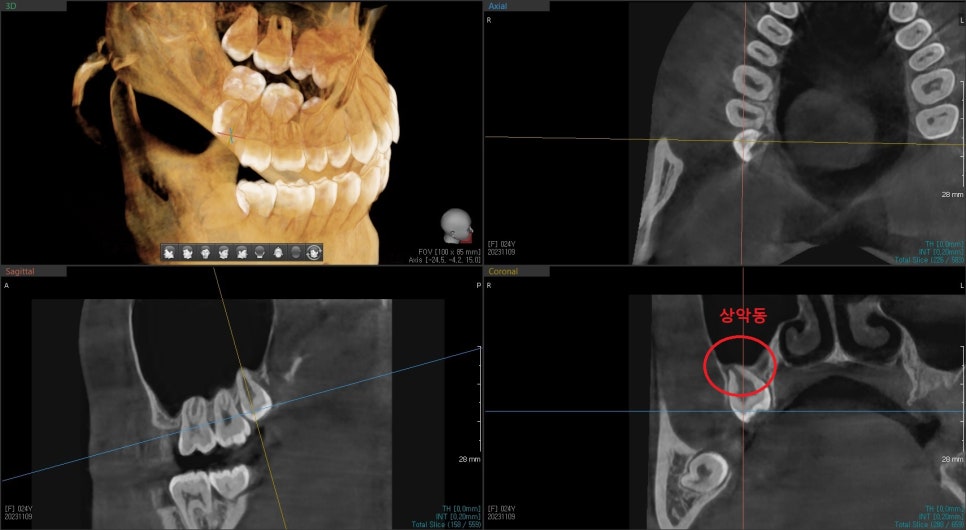

위쪽의 매복 사랑니는 치아도 작지만

상악동(=부비동)막과 연결되어 있고,

주변 뼈가 약한 경우에는

발치 과정 중에 치아가 상악동으로 들어가는 경우도 종종 있다고 합니다.

이런 일이 일어나더라도 결국은 빼지만

최대한 조심스럽게 발치를 시작했습니다.